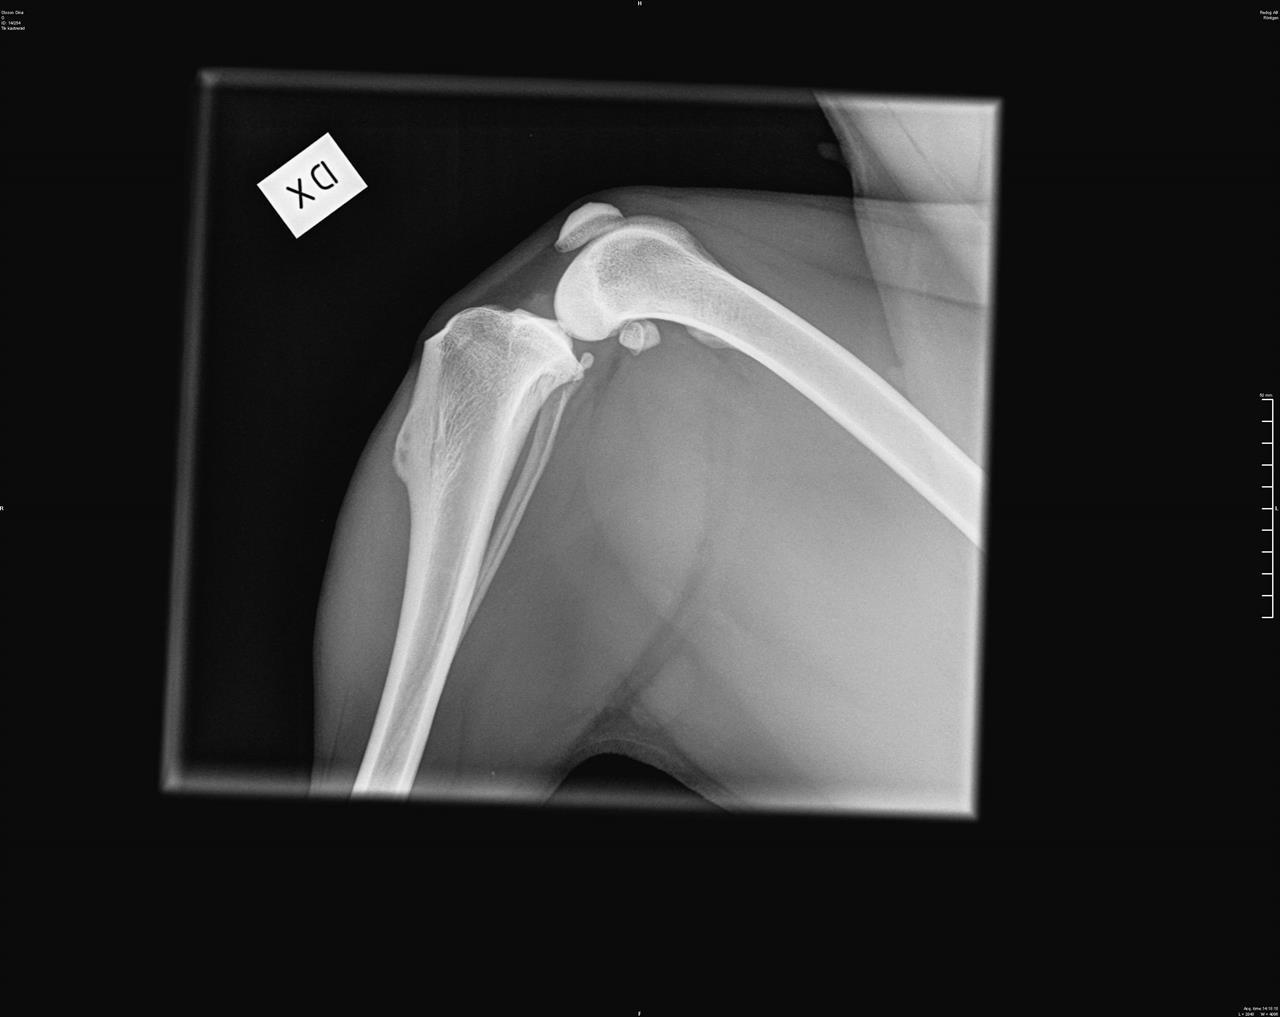

Röntgen

Hos oss röntgar vi med digital framkallning. Prisexempel: Höfter och armbågar 1900:-, endast höftleder 1400:- tillkommer gör SKK's avgift för avläsning och registrering.

OBS!

Innan röntgen måste remiss beställas via följande länk:

https://www.skk.se/sv/uppfodning/halsa/halsoprogram/bestall-rontgenavlasning/

Där står all information om tjänsten och hur man gör för att beställa röntgenavläsning.

Remissen kan inte beställas och betalas vid röntgentillfället utan ska skapas minst ett dygn före

röntgen.